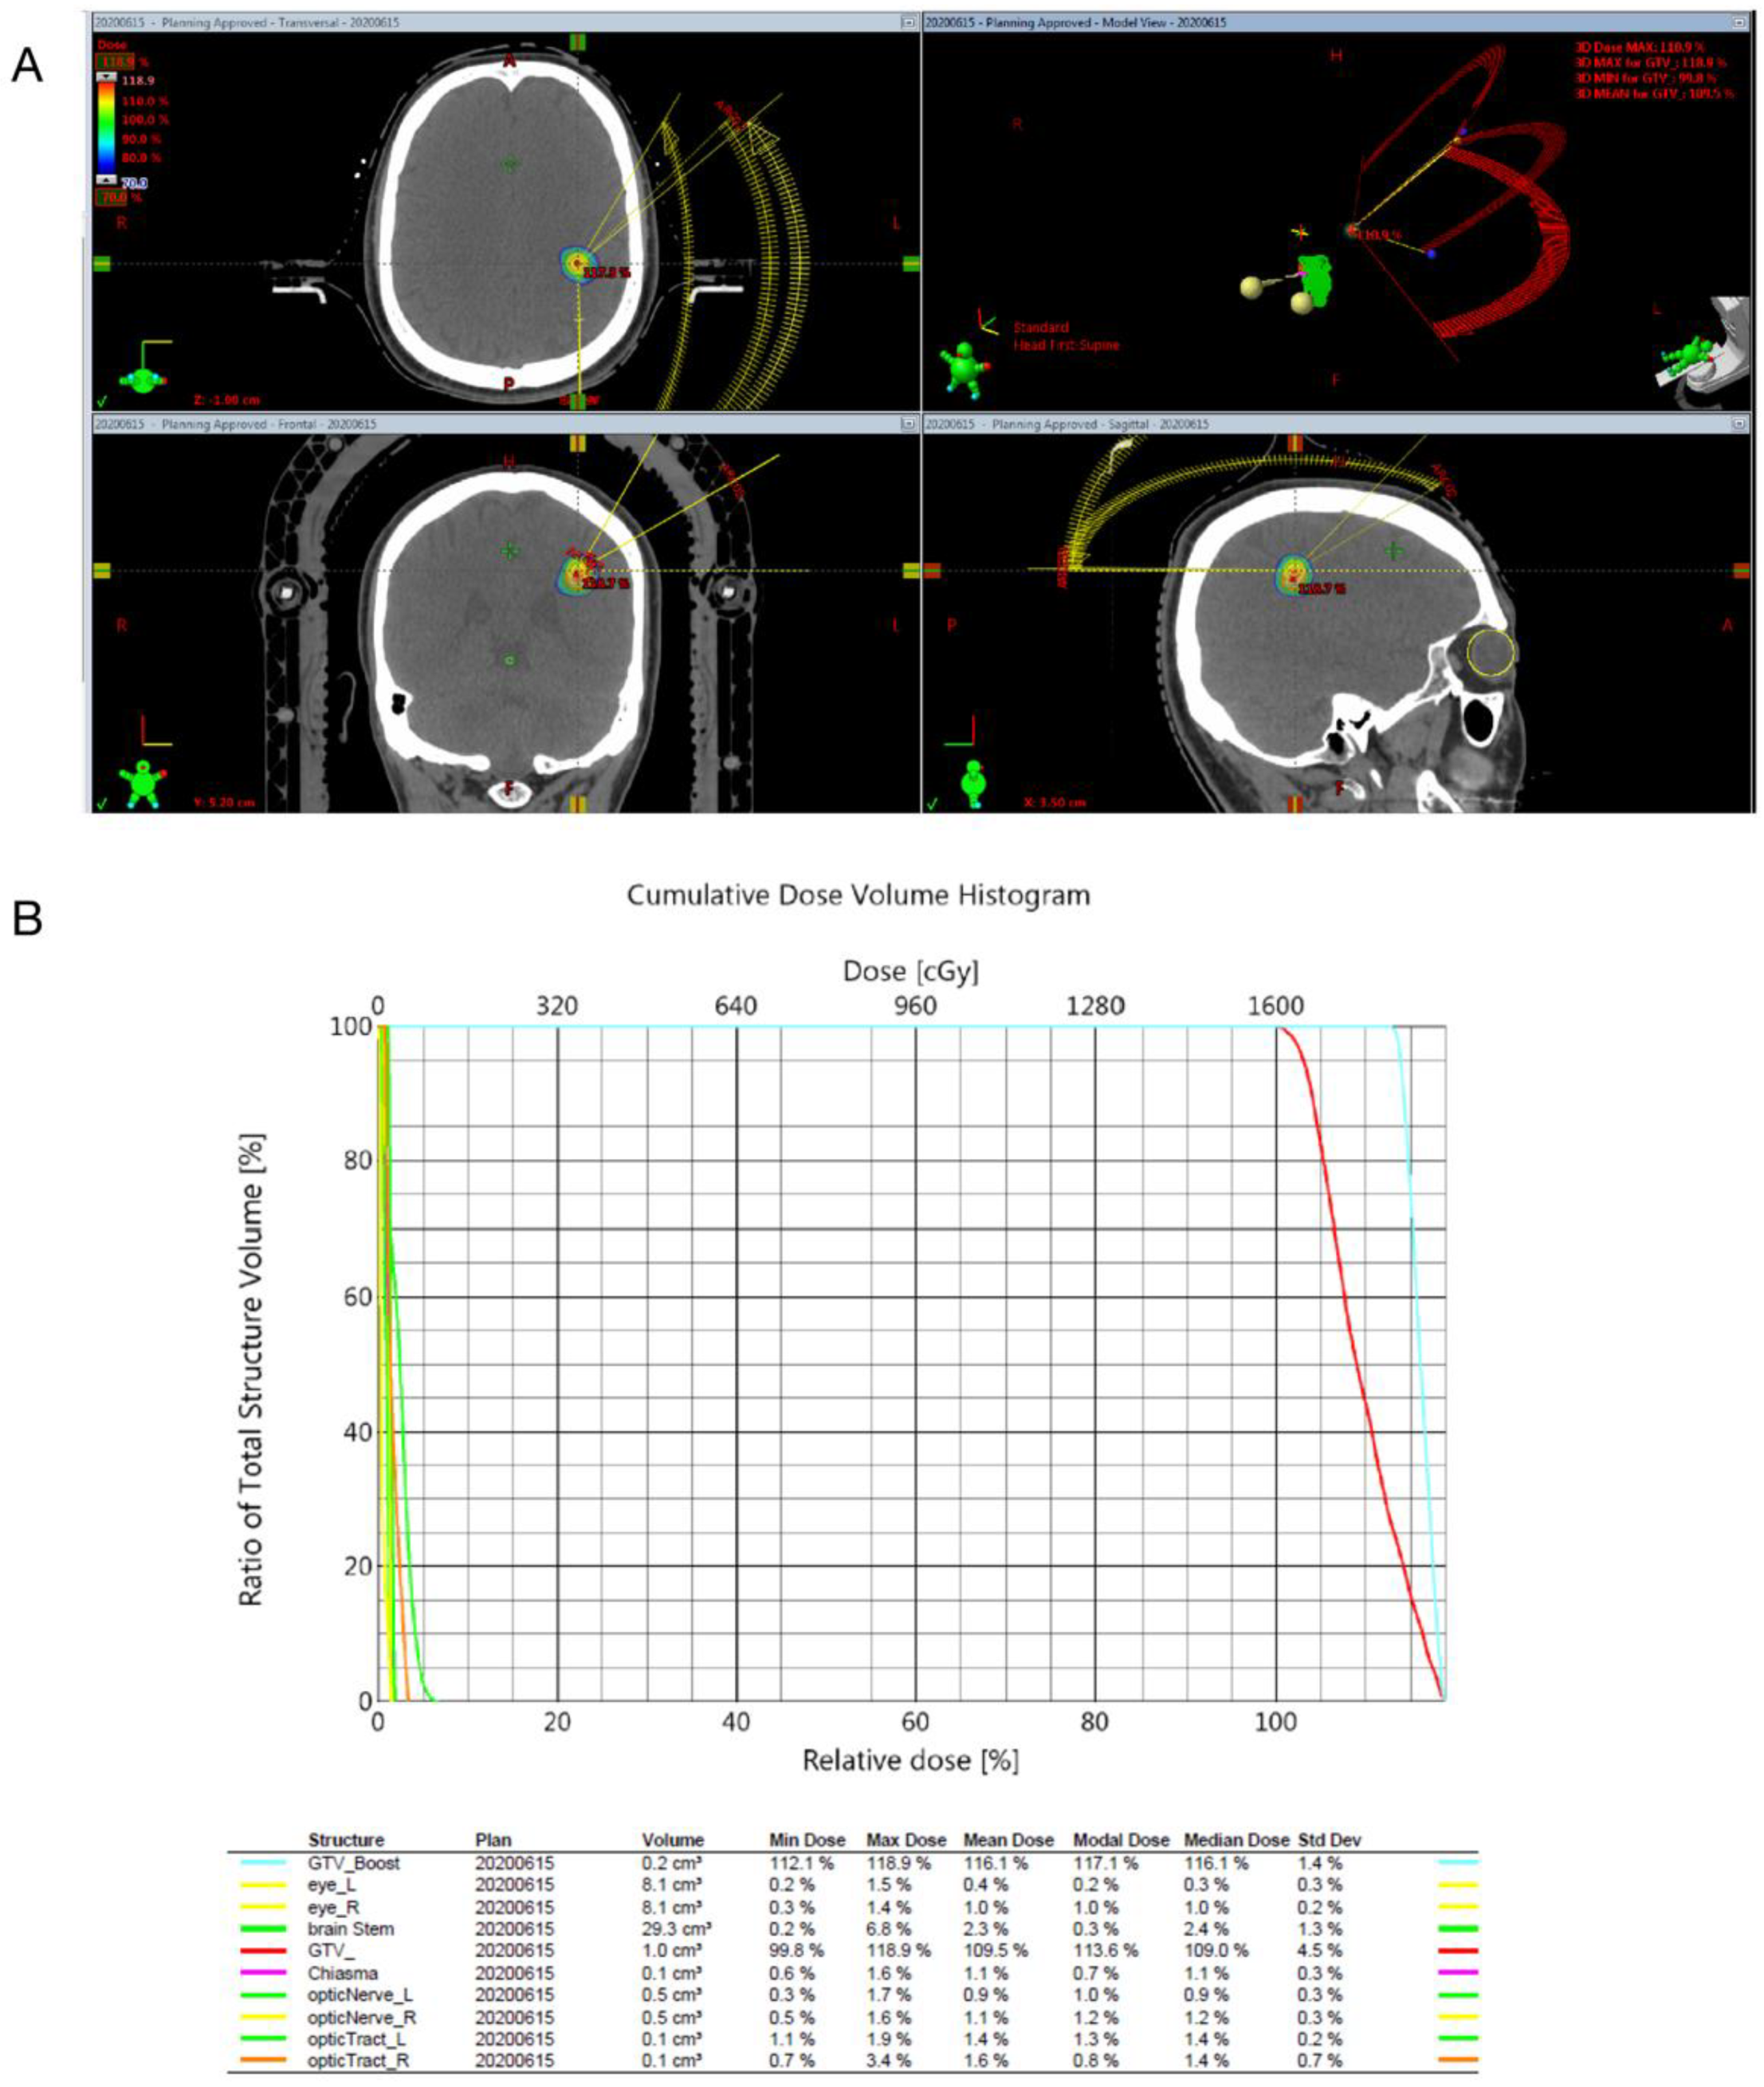

2.3. Radiosurgical Techniques